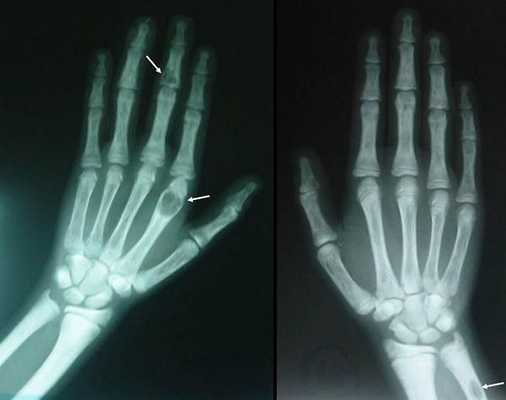

На поздней стадии костного гиперпаратиреоза происходит размягчение, искривления, патологические переломы (при обычных движениях, в постели) костей, возникают рассеянные боли в костях рук и ног, позвоночнике. В результате остеопороза челюстей расшатываются и выпадают здоровые зубы. Из-за деформации скелета больной может стать ниже ростом. Патологические переломы малоболезненны, но заживают очень медленно, часто с деформациями конечностей и образованием ложных суставов. На руках и ногах обнаруживаются периартикулярные кальцинаты. На шее в области паращитовидных желез можно пальпировать большую аденому.

Рентгенография позволяет обнаружить остеопороз, кистозные изменения костей, патологические переломы. Для оценки плотности костной ткани проводится денситометрия. При помощи рентгенологического исследования с контрастным веществом диагностируют возникающие при гиперпаратиреозе пептические язвы в желудочно-кишечном тракте. КТ почек и мочевыводящих путей выявляет камни. Рентгенотомография загрудинного пространства с пищеводным контрастированием бариевой взвесью позволяет выявить паратиреоаденому и ее местоположнение. Магнитно–резонансная томография по информативности превосходит КТ и УЗИ, визуализирует любую локализацию околощитовидных желез.

- костный гиперпаратиреоз — де формация конечностей, внезапные переломы, возникающие как бы сами по себе, остеопороз с возможными кистозными образованиями, болезнь Реклингхаузена;

Длительное течение заболевания сказывается на формировании костей. Так, н а поздних стадиях вовремя не диагностированного гиперпаратиреоза наблюдаются:

- разрушение дистальных или концевых фаланг конечностей;